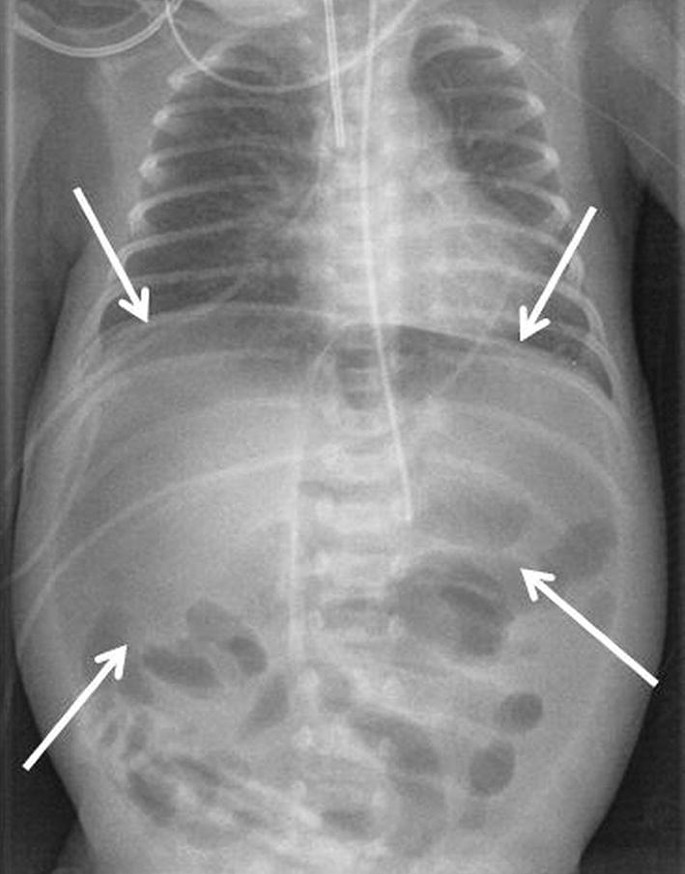

Department of radiology, university of kentucky college of medicine, 800 rose st, lexington, ky, 40536, usa. 1 department of radiology, north shore university hospital, manhasset, ny, usa. This patient is at high risk of perforation and/or bowel ischaemia. Mt niknejad md (radrounds radiology network member). Zurück zum zitat javors br, baker sr, miller ja (1999) the northern exposure sign: 05 tumors with coffee bean nucleus. Top free images & vectors for coffee bean sign radiology assistant in png, vector, file, black and white, logo, clipart, cartoon and transparent. Department of radiology, university of kentucky college of medicine, 800 rose st, lexington, ky, 40536, usa. • the apposed medial walls of the dilated bowel form a distinct oblique line that resembles the cleft of a. Looking for coffee bean sign in login? The coffee bean sign is a classic conventional radiographic finding of sigmoid volvulus. Alibaba.com offers 21,189 roasted coffee bean products. A wide variety of roasted coffee bean options are available to you, such as taste, variety, and processing type. Coffee time decor, coffee bean heart decor, coffee lovers gift, rustic wooden coffee sign, white and brown wall art, kitchen coffee sign. Surgery is recommended for patients with signs of bowel gangrene, peritonitis, or who fail nonoperative management 6. Rams horn stomach less than 4.00% patients of crohn's. Zurück zum zitat burgener fa, kormano m, pudas t (2011) differential diagnosis in conventional radiology. A classic finding in a patient with a sigmoid volvulus—the involved bowel wall is oedematous, and the contiguous walls form a coffee bean sign. The twisted loop of sigmoid colon is said to resemble a coffee bean. The coffee bean sign is a classic sign of sigmoid volvulus (fig. The coffee bean sign is a classic conventional radiographic finding of sigmoid volvulus. Amit chakraborty andres ayoob david disantis. Signs in radiology are usually based on many common objects or patterns that are easily. When the occluded intestinal loops are dilated with air (closed loop), the medial walls will touch and the inner line will create a coffee bean radiology 2003. Zurück zum zitat feldman d (2000) the coffee bean sign. Radiological imaging of the kidney. The coffee bean sign describes the appearance of the volvulus, with apposition of the medial walls introduction: Our patient and her family opted for comfort care only. There are 333 coffee bean sign for sale on etsy, and they cost sgd 30.09 on average. Management with rectal tube placement can often be attempted. A newly described finding in sigmoid volvulus.

X Ray Abdomen Supine Showing The Coffee Bean Appearance Of Sigmoid Colon Download Scientific Diagram. Zurück zum zitat burgener fa, kormano m, pudas t (2011) differential diagnosis in conventional radiology. The twisted loop of sigmoid colon is said to resemble a coffee bean. Top free images & vectors for coffee bean sign radiology assistant in png, vector, file, black and white, logo, clipart, cartoon and transparent. The coffee bean sign describes the appearance of the volvulus, with apposition of the medial walls introduction: This patient is at high risk of perforation and/or bowel ischaemia. Our patient and her family opted for comfort care only. Surgery is recommended for patients with signs of bowel gangrene, peritonitis, or who fail nonoperative management 6. Management with rectal tube placement can often be attempted. Signs in radiology are usually based on many common objects or patterns that are easily. 05 tumors with coffee bean nucleus. Zurück zum zitat feldman d (2000) the coffee bean sign. The coffee bean sign is a classic conventional radiographic finding of sigmoid volvulus. Mt niknejad md (radrounds radiology network member). 1 department of radiology, north shore university hospital, manhasset, ny, usa. Rams horn stomach less than 4.00% patients of crohn's.